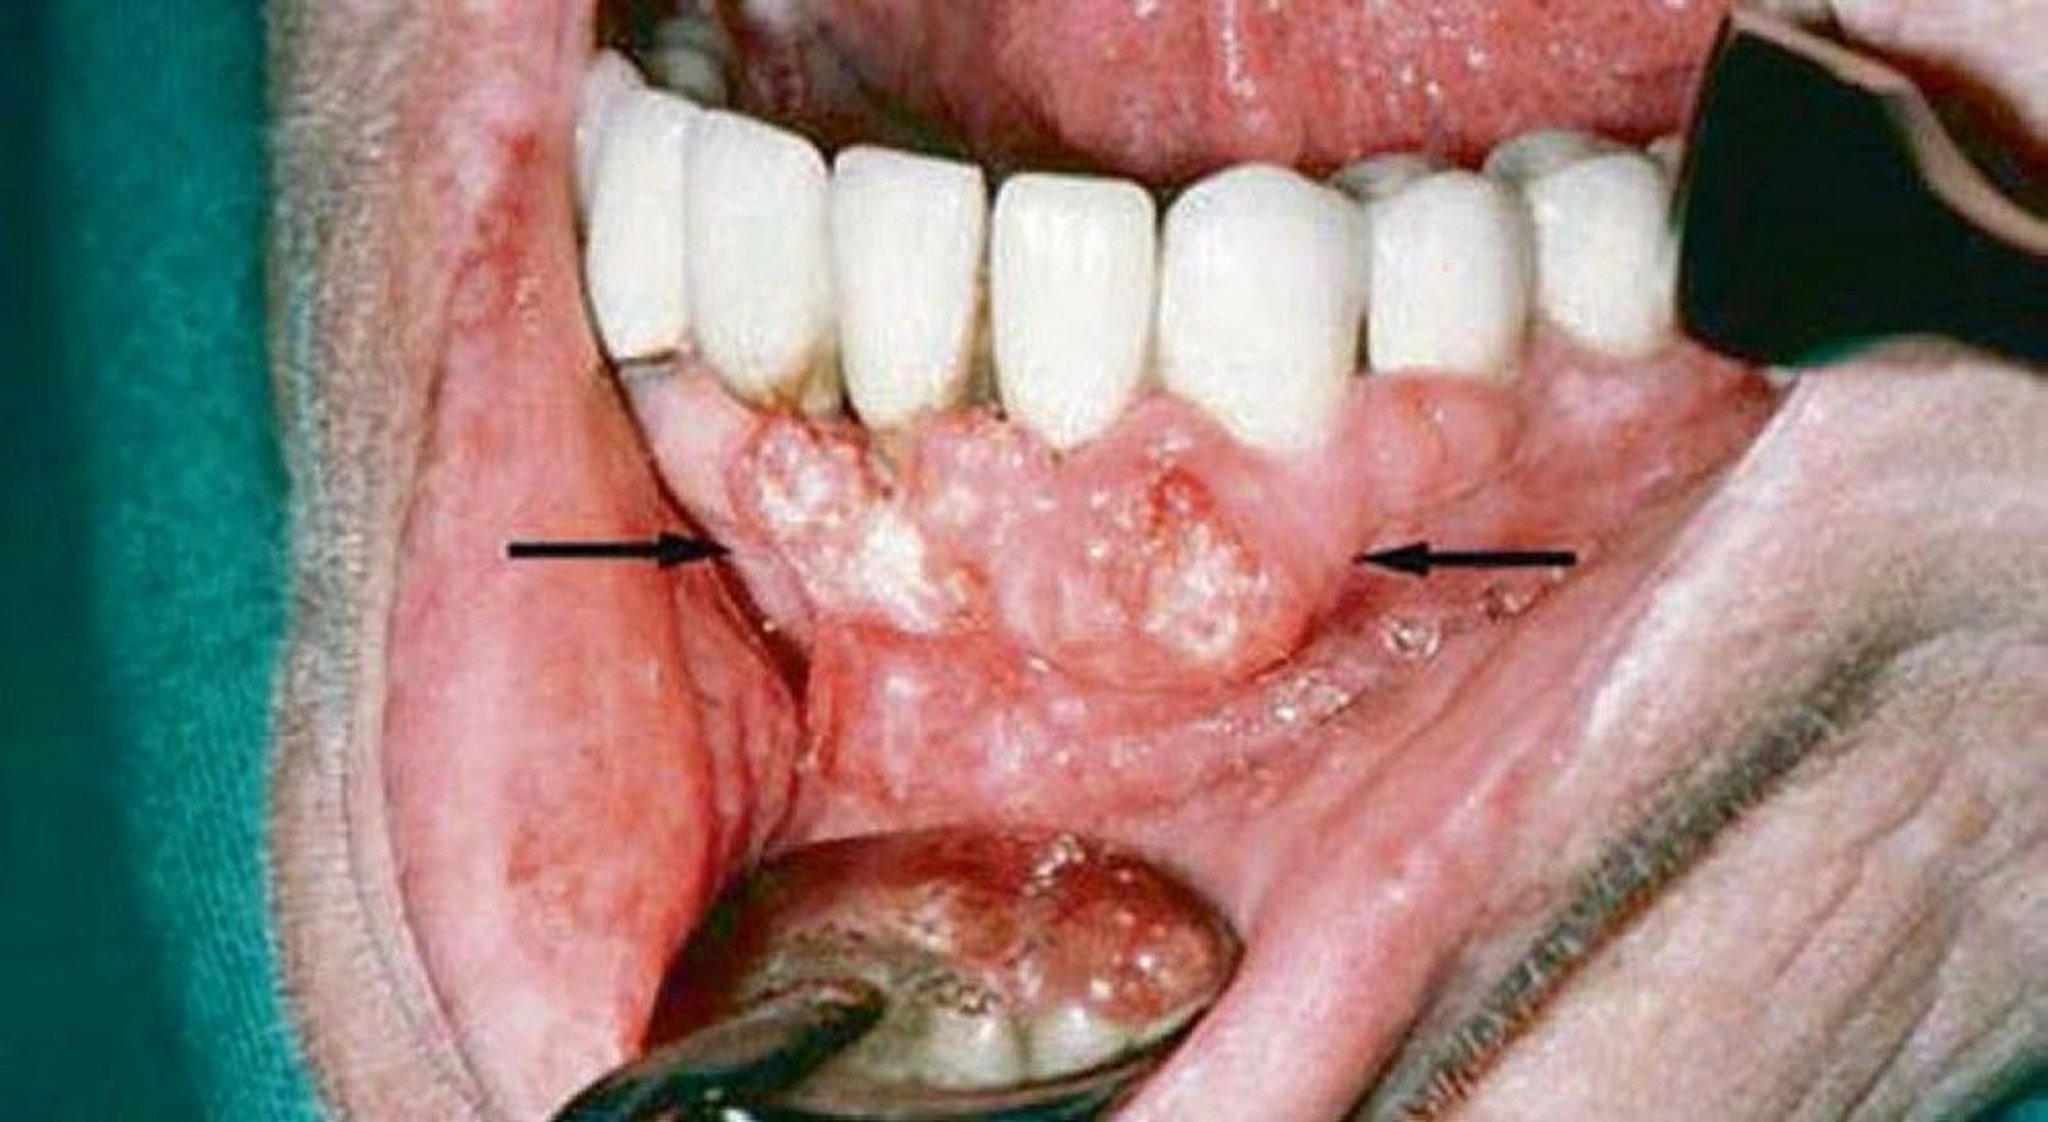

Squamous Cell Carcinoma (Gingival Lesions)

Gingival examination of this patient showed evidence of squamous cell carcinoma. Imaging studies showed invasion of the mandible.